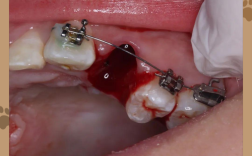

- 戴牙套: 确定方案后,预约时间进行矫治器(托槽或隐形牙套)的粘接或佩戴。

- 定期复诊: 通常每4-8周复诊一次,医生检查牙齿移动情况,调整加力。